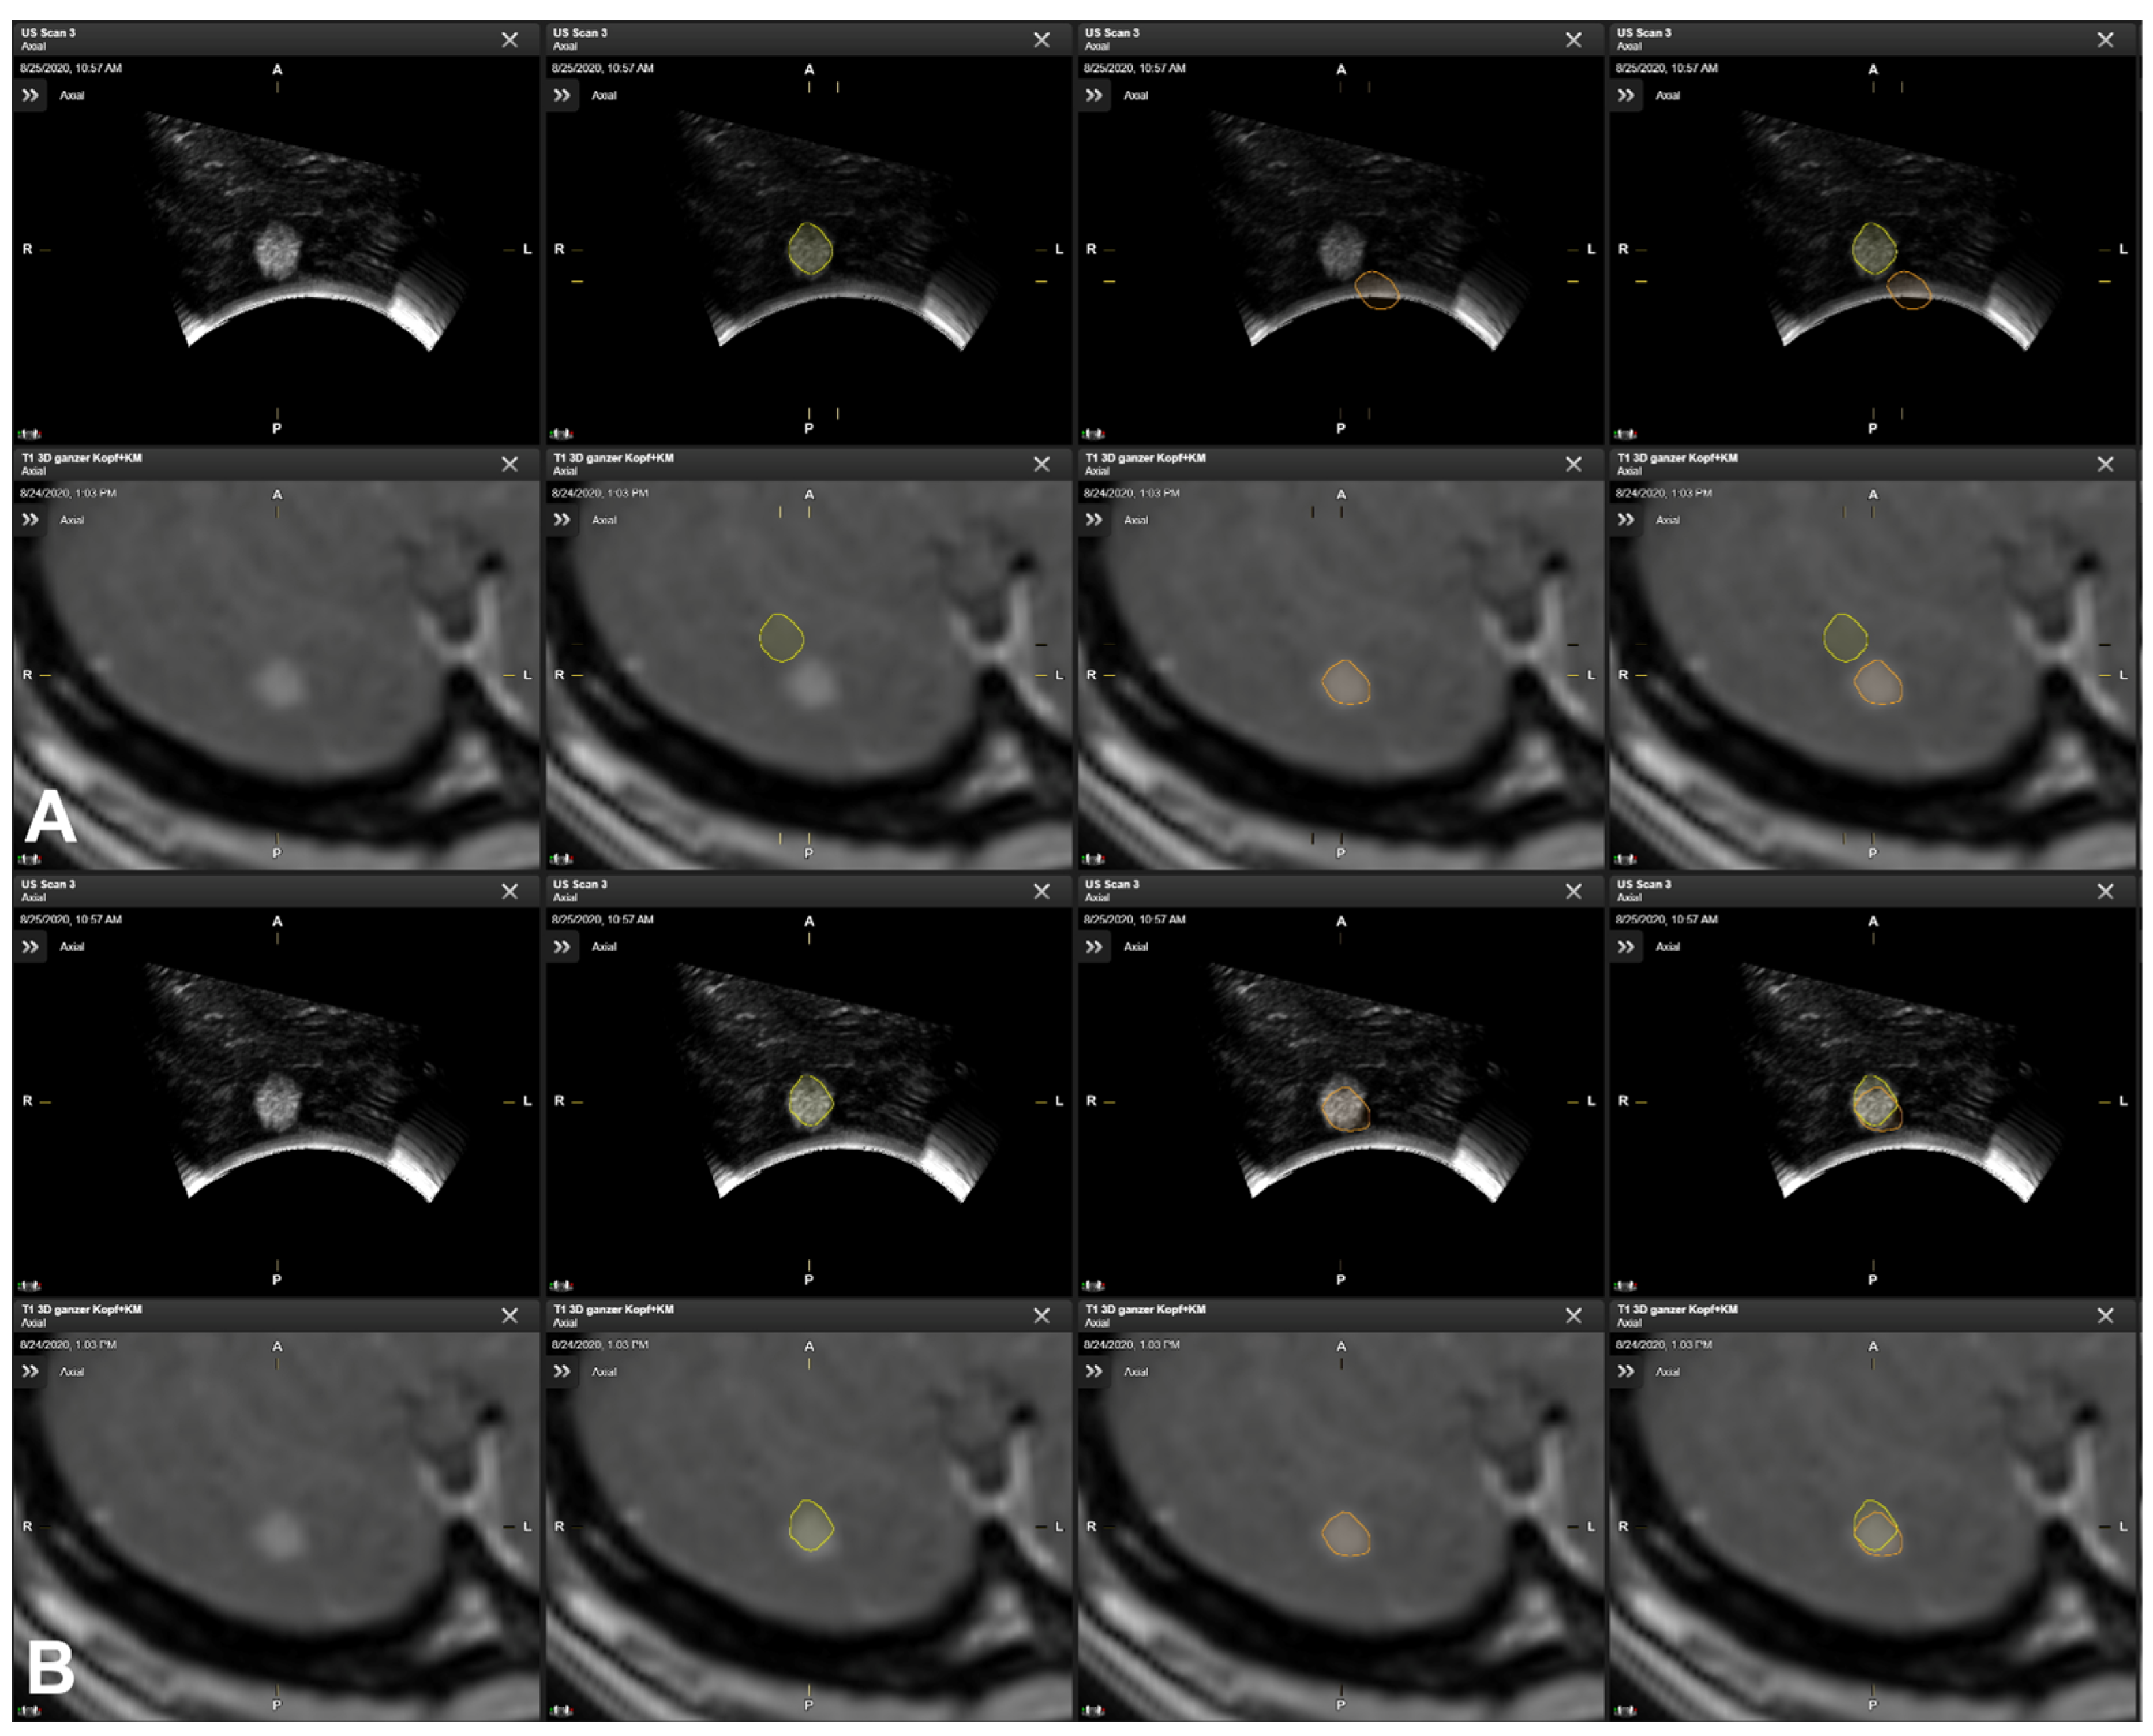

3.5. Illustrative Cases